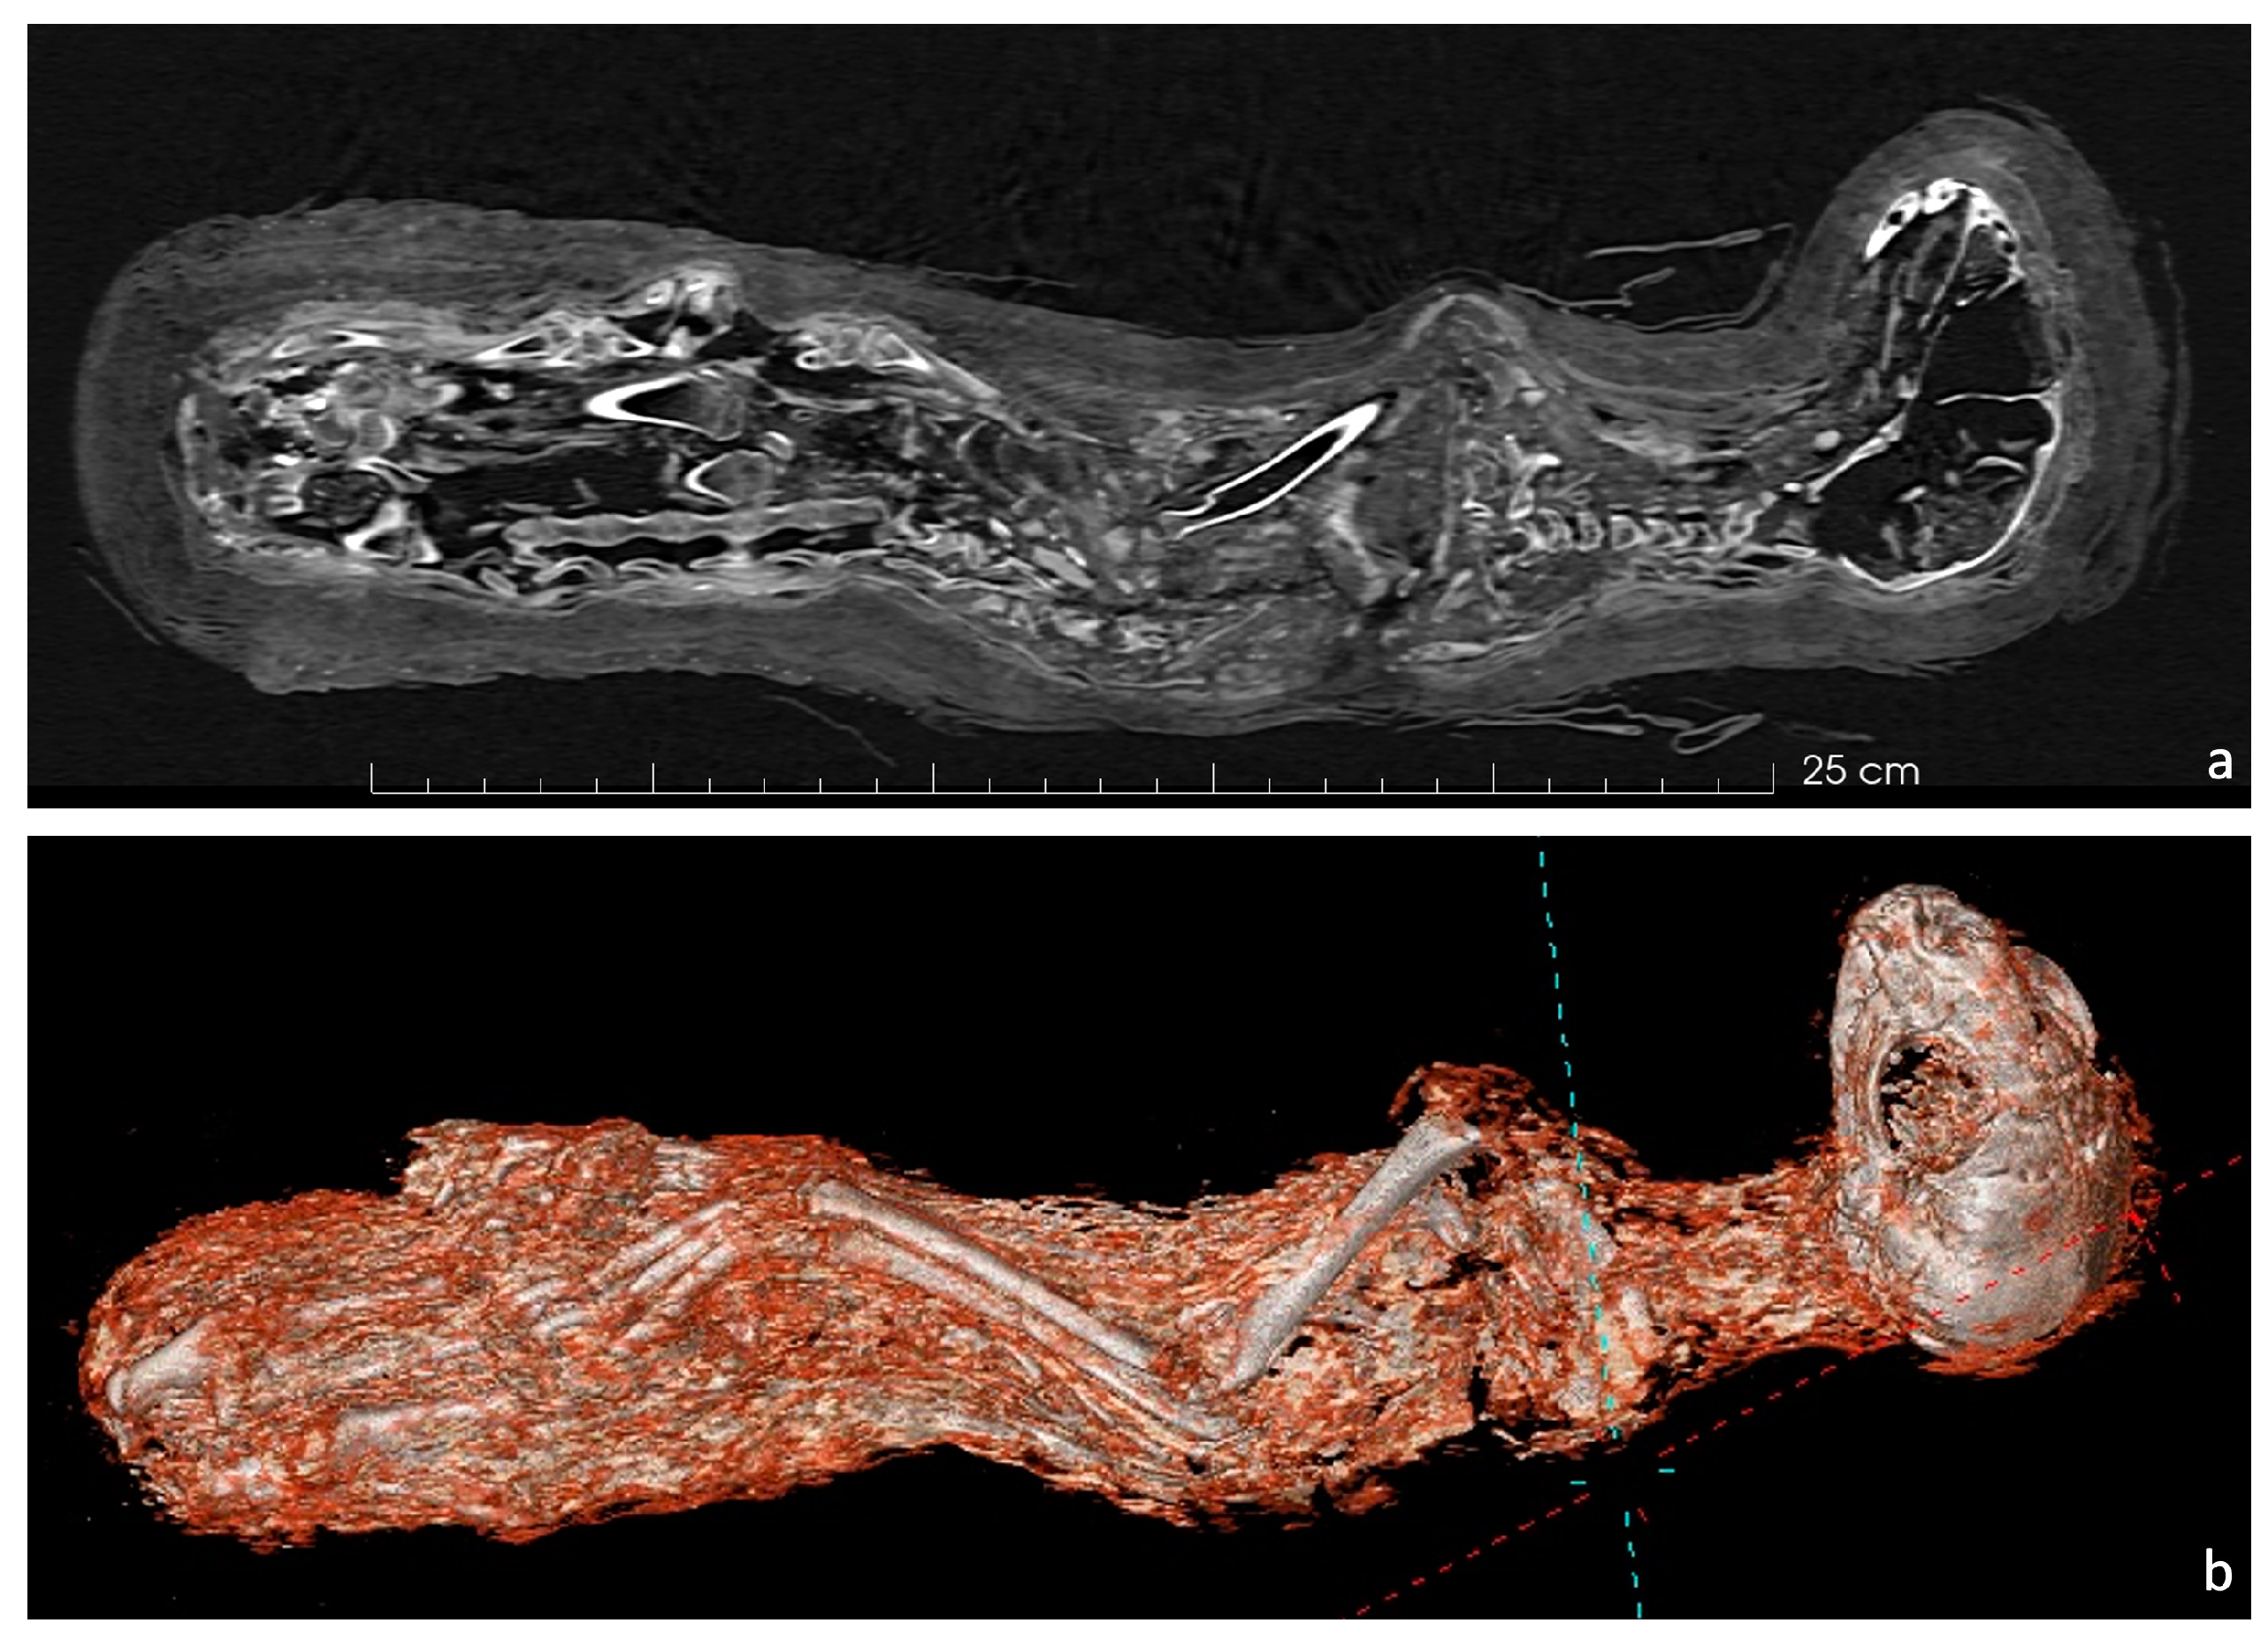

The CT scanner generated a DICOM-format dataset comprising 512 × 512 pixel 2D slice images, providing a detailed visualization of both the skeletal and soft tissue components. These images facilitated an in-depth investigation of the mummy’s internal structures. Parallel orthogonal slices resulting from the CT scanning were used to build a 3D model using AVIZO 3D Pro 2022 software (Thermo Fisher Scientific Inc., Waltham, MA, USA), enabling further elaborations. A semi-automatic threshold-based segmentation was used to separate some of the bones from the bandages and soft tissues [38,39,40]. Measurements were recorded using AVIZO software on 3D models of the bones following von den Driesch (1979) [41]. The sagittal reconstruction (Figure 2a) clearly outlines the skeletal features, offering a non-invasive approach to assess the preservation of the bones and detect any potential anomalies or pathological conditions. Additionally, the three-dimensional volume-rendered (VR) model (Figure 2b) offers a comprehensive reconstruction of the mummy, enabling the examination of the wrapping patterns and the identification of any artifacts placed inside during the mummification process. The age at death was established considering the epiphyseal fusion and teeth’s eruption, following available data in the literature [42,43,44,45].

Figure 2.

(a) CT scan (MRP sagittal reconstruction) and (b) three-dimensional reconstructed model of the cat mummy.

The CT data reveal a complete skeleton of the cat (Figure 2a). Like most other case studies [15,46,47,48], the mummified cat is in a sitting position: its forelimbs are stretched out along its body, while its hind limbs are flexed and pushed in toward its belly. Lastly, the tail is folded between its hind and fore legs, lying along the belly.